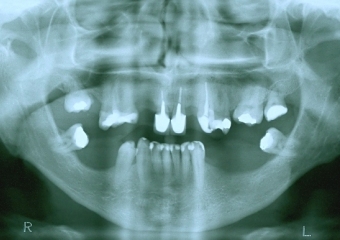

Raio - x inicial em 2009 - Clínica Cliniface

Raio - x inicial em 2009